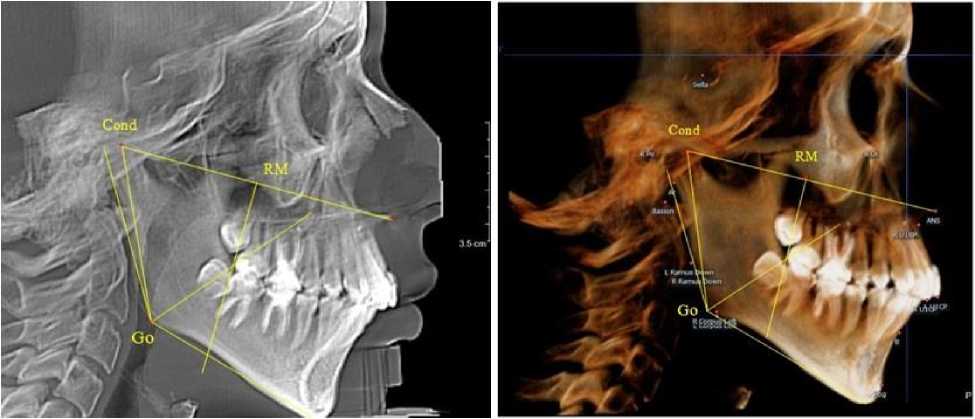

Биссектриса угла Cond-Go-Ме (стресс-ось), так же, как и на ортопантомограмме, располагались позади от формирующихся зачатков первых постоянных моляров нижней челюсти (рис. 4).

Рис. 4. Особенности боковой телерентгенограммы (а) и 3D-модели (б) ребенка 4 лет в периоде прикуса молочных зубов

Зачатки вторых постоянных моляров нижней челюсти располагались кпереди по отношению к биссектрисе угла Go´-Go-Ме, что так же, как и на верхней челюсти, оказывало благоприятное влияние на формирование и прорезывание нижнего первого моляра. При анализе боковых телерентгенограмм и трехмерной модели установлено, что положение зубов и челюстей относительно реперных линий было близким по значениям, полученным при анализе ортопантомограмм. Биссектриса угла Cond-Go-Ме, так же, как и на ортопантомограмме, располагались позади от формирующихся зачатков вторых постоянных моляров нижней челюсти (рис. 6).

а                                     б

Рис. 6. Особенности боковой телерентгенограммы (а) и 3D-модели (б) ребенка 7 лет после прорезывания 1-й группы постоянных зубов

При анализе боковых телерентгенограмм и трехмерной модели установлено, что положе- ние зубов и челюстей относительно реперных линий было близким по значениям, полученным при анализе ортопантомограмм. Биссектриса угла Cond-Go-Ме, так же, как и на ортопантомограмме, располагались позади от формирующихся зачатков вторых постоянных моляров нижней челюсти (рис. 8).